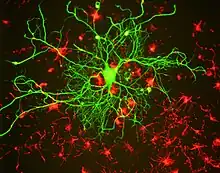

Neurofilament light polypeptide, also known as neurofilament light chain, abbreviated to NF-L or Nfl and with the HGNC name NEFL is a member of the intermediate filament protein family. This protein family consists of over 50 human proteins divided into 5 major classes, the Class I and II keratins, Class III vimentin, GFAP, desmin and the others, the Class IV neurofilaments and the Class V nuclear lamins. There are four major neurofilament subunits, NF-L, NF-M, NF-H and α-internexin. These form heteropolymers which assemble to produce 10nm neurofilaments which are only expressed in neurons where they are major structural proteins, particularly concentrated in large projection axons. Axons are particularly sensitive to mechanical and metabolic compromise and as a result axonal degeneration is a significant problem in many neurological disorders. The detection of neurofilament subunits in CSF and blood has therefore become widely used as a biomarker of ongoing axonal compromise. The NF-L protein is encoded by the NEFL gene.[5][6] Neurofilament light chain is a biomarker that can be measured with immunoassays in cerebrospinal fluid and plasma and reflects axonal damage in a wide variety of neurological disorders.[7][8] It is a useful marker for disease monitoring in amyotrophic lateral sclerosis,[9] multiple sclerosis,[10] Alzheimer's disease,[11][12] and more recently Huntington's disease.[13] It is also promising marker for follow-up of patients with brain tumors.[14] Higher levels of blood or CSF NF-L have been associated with increased mortality, as would be expected as release of this protein reflects ongoing axonal loss.[15] Recent work performed as a collaboration between EnCor Biotechnology Inc. and the University of Florida showed that the NF-L antibodies employed in the most widely used NF-L assays are specific for cleaved forms of NF-L generated by proteolysis induced by cell death.[16] Methods used in different studies for NfL measurement are sandwich enzyme-linked immunosorbent assay (ELISA), electrochemiluminescence, and high-sensitive single molecule array (SIMOA).[17]

Neurofilament assembly and structure